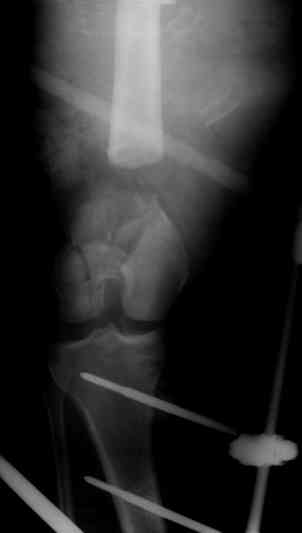

Больной 19 ти лет, пострадал в результате ДТП, пассажир мотоцикла. Получил открытый оскольчатый перелом н/3 левой бедренной кости 3a тип по Гастилло-Андерсену. При поступлении ПХО ран, фиксация стержневым аппаратом наружной фиксации. Лечение больного осложнилось развитием анаэробной флегмоны левого бедра. Лампасные разрезы, неоднократные некрэктомии, некротизировался участок диафиза левой бедренной кости на протяжении 15 см. Произведена резекция. 20.05.10- демонтаж АНФ, остеоситез левой бедренной кости гибридным циркулярно-монолатеральным стержневым дистракционным аппаратом наружной фиксации, остетомия левой бедренной кости в в/3. Сейчас начата дистракция в аппарате, проводится подготовка ран к аутодермопастике.